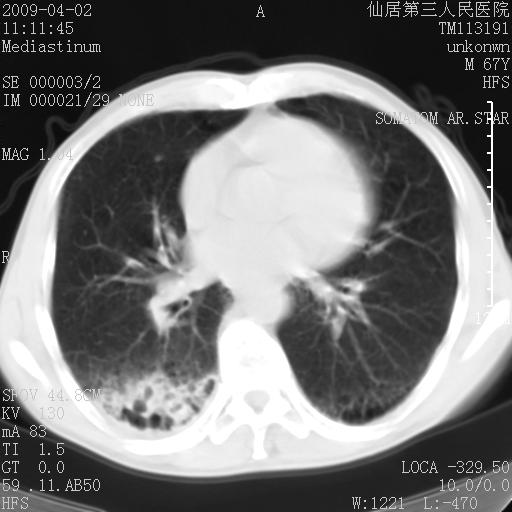

患者老年男性,乏力畏寒来诊,摄胸片示右下肺感染性病变,抗炎两周后复查胸片,无好转有进展。

后做ct平扫表现如下:

考虑右肺炎症可能性大,不除外细支气管肺泡癌

是否还要考虑肺间质纤维化,建议hrct扫描。

考虑间质性肺炎。

病灶呈蜂窝征,纵隔多个淋巴结肿大;肺泡癌需考虑

右肺下叶背段干酪性肺炎。请痰检[emb28]

我认为普通的感染应该可以除外,间质性肺炎可能性较大,但如何解释纵膈的淋巴结肿大呢

考虑双肺间质性改变(间质纤维化?)伴右肺下叶感染。